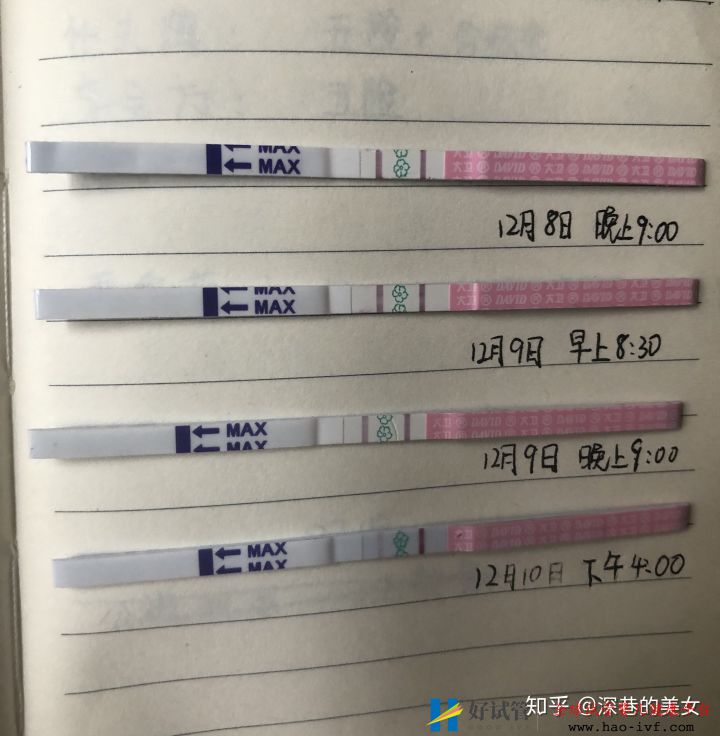

9月15号测了一下试纸,还是有印。估计打的绒促还没代谢完。

9月18号,早晚又测了一下试纸还是有印。我的代谢可真慢。今天体温上升到37.2。是我没有过的体温,腰也有点酸,晚上刷牙还吐了。种种表现很像有了,但是我心里没底。最终我发现医生让我每天吃的黄体酮有副作用,会引起发热、恶心、失眠。哈哈哈哈 全给对上了。这个月凉凉啦。正好离职了,继续备孕奋斗。

9月21日,绒促第13天,早上测的是有一根有印,一根白板。我真的是懵了。这几天晚上一直睡不好觉,夜里总是醒来好几次,而且容易想去上厕所。忍了两天没有测,结果也是不太好。哎。有的时候折磨我的不是结果,而是过程。晚上做梦,梦到自己的试纸是特别明显的双杠。开心的我不行了。然后惊醒了。五点就起床验孕了。结果不太好。本来前几天腰酸、体温高、恶心。结果这几天这些症状也消失了。我对自己失望了。估计是第一次吃黄体酮,身体产生的反应。但是期望老天眷顾我一下。

9月22号,绒促14天,试纸白板。心里五味杂陈。停药等月经干净后去做输卵管造影。

10月5号。输卵管造影介绍。两侧输卵管通而不畅。求子之路算是走了一大半。最担心的事情已经放下了。虽然几率小一些,但还是放松心情好好备孕。因为我预感我的哆啦就要来了。